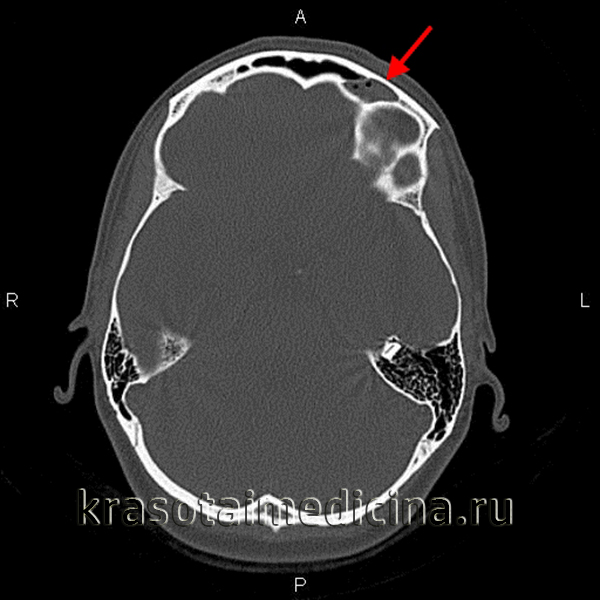

- Комп’ютерна томографія. КТ навколоносових пазух призначається при низької діагностичної цінності рентгенографії, підозрі на розвиток орбітальних або інтракраніальних ускладнень. На томограмі чітко відображаються всі наявні зміни кісткових структур і вхідного каналу.

КТ придаткових пазух носа. Вміст з включеннями газу в лівій лобовій пазусі